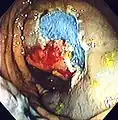

Polyp is identified.

Polyp is identified. A sterile solution is injected under the polyp to lift it away from deeper tissues.

A sterile solution is injected under the polyp to lift it away from deeper tissues. A portion of the polyp is now removed.

A portion of the polyp is now removed. The polyp is fully removed.

The polyp is fully removed.